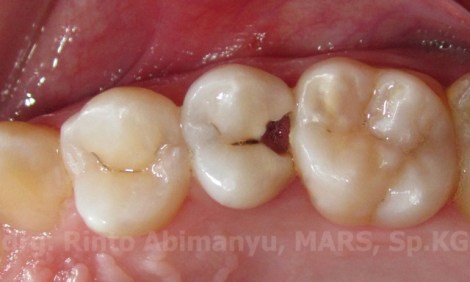

Setelah melakukan anamnesa yang diperlukan saya lakukan pemeriksaan klinis, terlihat gigi 15 karies di bagian distal dan memang kavitasnya agak besar di bagian dalam sehingga kalau kemasukan makanan akan sulit keluar..

Ini kondisi awal gigi 15…